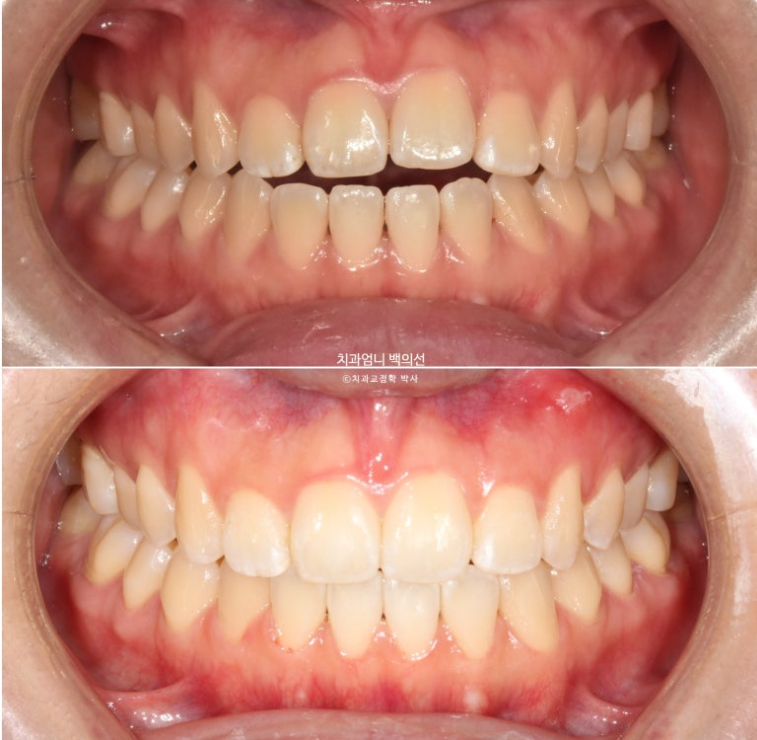

24년 12월에 재교정을 위해 내원하신 분 입니다.

중학교때 교정을 했으나 철사유지장치가 떨어지면서 앞니가 다시 틀어진 상태입니다.

앞니 높낮이 단차와 개방교합도 보입니다.

파란 화살표 송곳니는 안쪽으로 쓰러져 있습니다.

위 앞니 하나가 올라간 것은 철사가 떨어져서가 맞습니다.

파란 화살표 접착제가 까맣게 보이는 것은 접착제가 치아와 분리된 상태이기 때문입니다.

맞아진 앞니 높낮이와 적절한 앞니 교합

앞니 개방교합이 깔끔하게 해결되었습니다.

이제 전후 비교 보겠습니다.

24.12~25.06

개방교합 뿐 아니라 철사의 변형으로 쓰러져 있던 송곳니도 세웠습니다.

6개월간 앞니 부분교정의 변화 치고 드라마틱 합니다.